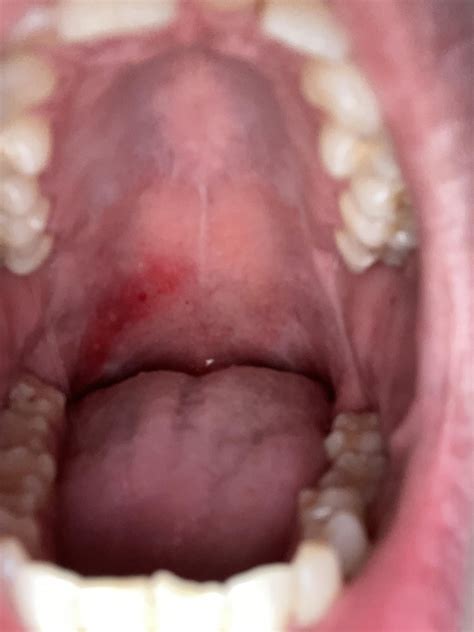

The back of the mouth, also known as the oropharynx, is a critical part of the digestive and respiratory systems. It is located behind the oral cavity and extends down to the larynx and esophagus. The oropharynx is lined with mucous membranes and contains several important structures, including the tonsils, uvula, and soft palate.

The tonsils, located on either side of the throat, are part of the lymphatic system and play a role in immune defense. The uvula, a small, fleshy piece of tissue that hangs down from the soft palate, helps to close off the nasal passages during swallowing. The soft palate, a muscular structure at the back of the roof of the mouth, also aids in swallowing and speech.

Common Issues Affecting the Back of the Mouth

Several conditions can affect the back of the mouth, leading to discomfort, pain, or difficulty in swallowing and speaking. Some of the most common issues include:

• Tonsillitis: Inflammation of the tonsils, often caused by a viral or bacterial infection.

• Sore Throat: Pain or irritation in the throat, which can be caused by various factors, including infections, allergies, or dry air.

• Postnasal Drip: Excess mucus in the back of the throat, often caused by allergies, sinus infections, or colds.

• Tonsil Stones: Small, hard deposits that form in the tonsils, often due to trapped food particles or bacteria.

• Oropharyngeal Cancer: Cancer that affects the oropharynx, often caused by factors such as smoking, alcohol use, or the human papillomavirus (HPV).

If you experience persistent symptoms or discomfort in the back of the mouth, it is essential to consult a healthcare professional for proper diagnosis and treatment.